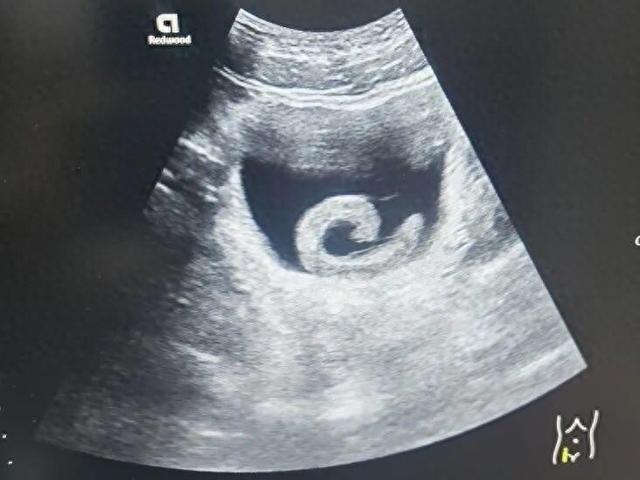

泌尿外科副主任医师马曜辉为小郑进行了经尿道膀胱异物取出术,手术顺利,解除了尿道梗阻,小郑的疼痛也瞬间消失。事后,小郑对自己的行为感到后怕和悔恨。